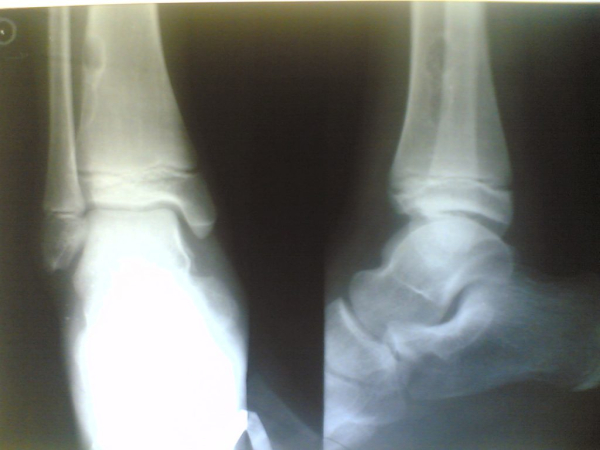

Рентгенография определит очаг деструкции. Размер такой области 5—8 см в длину. Хондромиксоидное образование на снимках выглядит как зона просветления с четкими очертаниями зоны поражения, вокруг нее присутствует склеротический ободок. Корковый слой над источником поражения может быть разбухший и истонченный. Если опухоль образовалась в области позвоночника, возможно прорастание надкостницы. Для более точного диагноза онколог проведет ряд дополнительных обследований, которые могут включать биопсию тканевых участков опухоли и иммуногистохимическое исследование. Суть метода иммуногистохимического исследования заключается в идентификации специфичных антигенных свойств злокачественных опухолей. По результатам диагностики определяют структуру опухоли и присутствие в ней раковых клеток.